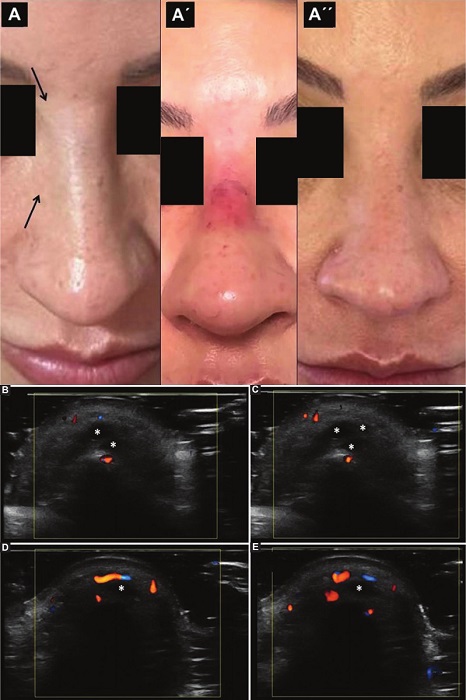

En el grupo 2 (n = 30, 36% del total de pacientes), 14 (46,6%) pacientes sufrieron complicaciones agudas y 16 (53%) presentaron complicaciones crónicas. Se consideraron agudas las complicaciones que surgieron dentro del mes del procedimiento estético.

Además, de los 14 pacientes que presentaron complicaciones agudas, cinco requirieron un tratamiento específico bajo guía ecográfica. Las complicaciones agudas estuvieron relacionadas con pacientes con compromiso vascular por inyección de material de relleno intraarterial (compromiso de arterias columelares, nasal dorsal y facial), sobre corrección por exceso de producto, irritación/trauma de nervios infraorbitarios, nódulos inflamatorios y edema difuso (Figs. 4 y 5). Con respecto a las complicaciones crónicas se encontraron nódulos tardíos, edema tardío intermitente y persistente (ETIP), infección subaguda/ tardía, y migración/redistribución de rellenos permanentes y no permanentes (Figs. 6, 7 y 8). Además, cabe señalar que el 97% (29) de los integrantes de este grupo presentaban rellenos previos (24 con AH y 5 con rellenos permanentes).

Además, dentro de las complicaciones agudas, encontramos todo el espectro relacionado con el compromiso vascular, ya sea por inyección intravascular inadvertida del material de relleno o por compresión extrínseca. Si no se resuelve a la brevedad, podrían desencadenar trastornos en la irrigación tisular con eventual necrosis. Este aspecto es sumamente importante dadas las grandes anastomosis entre el sistema carotídeo interno y externo, por ejemplo, un compromiso vascular del sistema carotídeo externo podría comprometer a la arteria oftálmica ocasionando ceguera y hasta eventos vasculares intracraneales. En nuestro trabajo, evidenciamos a un paciente con compromiso de la arteria nasal dorsal, a otro con obstrucción de arterias columelares y un tercero que presentó compromiso de la arteria facial a la altura del surco nasogeniano; todos ellos requirieron la resolución del cuadro mediante la inyección de hialuronidasa con guía ecográfica. En este tipo de complicaciones, sabemos que la ecografía Doppler facial proporciona información relevante para dirigir la inyección de hialuronidasa al lugar preciso de afectación, utilizando menor cantidad de enzimas y con una resolución más rápida18.

A las complicaciones que suelen desarrollarse luego del mes del procedimiento estético se las entiende como crónicas. Estas son frecuentes en pacientes con rellenos permanentes, debido a su redistribución/ migración con la consecuente deformación de la región del rostro. En nuestro trabajo, todos los pacientes con este tipo de rellenos tenían algún grado de deformación. Esto puede suceder, aunque menos frecuentemente, con rellenos de AH, quizás debido a errores en la técnica inicial; sin embargo; una vez diagnosticados, suelen revertirse fácilmente con la inyección de hialuronidasa19.

Con respecto al ETIP, descrito por primera vez por Cavallieri et al.22 en el año 2017, se caracteriza por edema local tardío, de carácter intermitente, desencadenado por cuestiones específicas (p. ej., enfermedad, vacunación) y que persiste mientras exista la presencia de AH localmente. En nuestro trabajo encontramos tres pacientes con este tipo de cuadro, todos en la región infraorbitaria. Gracias al aporte ecográfico, se pudo diagnosticar que el motivo del edema eran los depósitos de AH no degradados que estaban rodeados por edema de tejidos circundantes. Todos ellos se beneficiaron con la inyección de hialuronidasa.